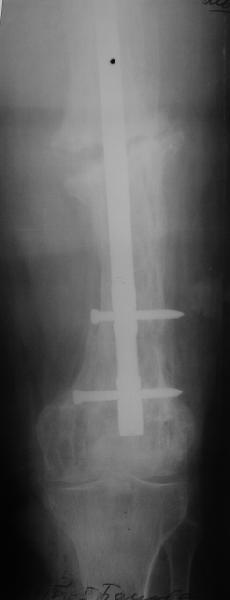

Re: перелом бедра на фоне болезни Педжета

Еще один пример. Пациентка с юга России, прислала рентгенограммы через год. На сегодня прошло 2 г. 8 мес. после операции. Несмотря на не очень убедительный процесс сращения, пациентка ходит. Учитывая остеопороз при Педжете, решили, что динамизировать вообще не нужно.